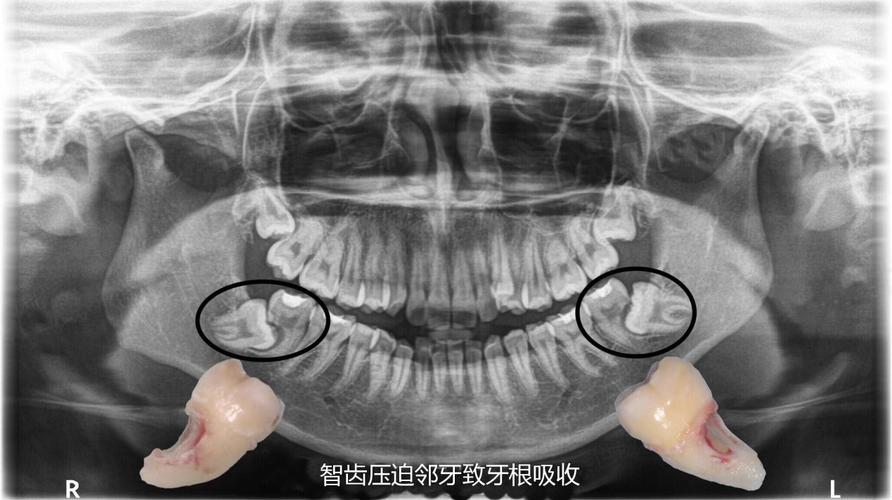

- 根尖片:常规检查手段,可显示牙根长度、形态变化,但对颊舌向吸收敏感度低;

- 曲面断层片:用于评估全口牙根吸收情况,但存在影像重叠,易漏诊轻微吸收;

- CBCT:目前诊断金标准,可三维、多层面显示牙根吸收的部位、范围和程度,精准量化吸收量(如吸收深度占根长比例)。

- 分类标准:根据吸收程度可分为:

- 轻度:吸收<根长1/3,牙根形态基本完整;

- 中度:吸收达根长1/3-2/3,牙根可见明显凹陷或变短;

- 重度:吸收>根长2/3,牙根显著缩短或仅残留根尖部,可能影响牙齿稳固性。